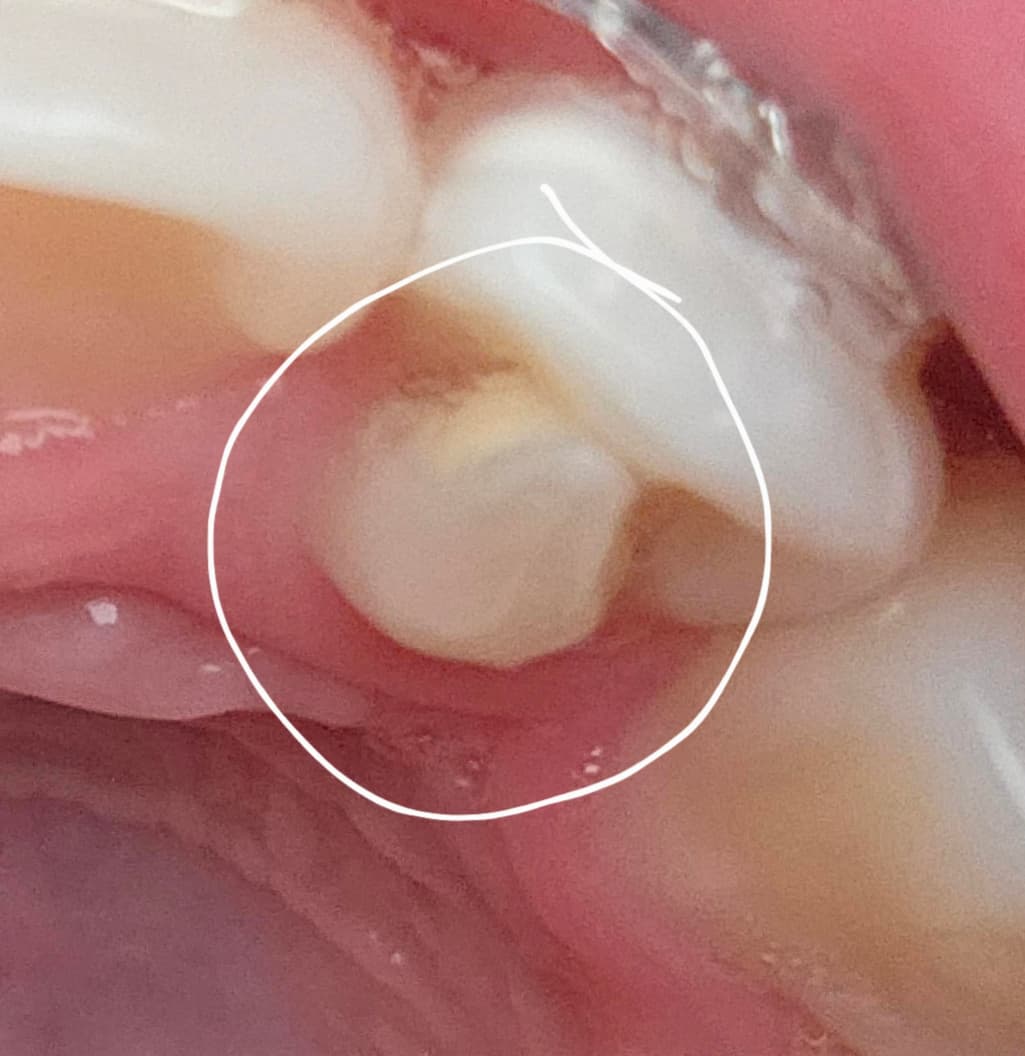

작은 앞니의 표시된 부분은 그대로 두는게 좋을까요?

가끔 아래쪽 작은앞니와 송곳니에 닿아서 아래쪽 치아가 조금 갈린 느낌이 있습니다.

치아의 돌기로 인해서 교합간섭이 생기거나 불편감이 잇다면 조정을 해주는것이 좋습니다. 그렇지 않았을 경우 치아에 불필요한 힘으로 인해서 손상이나 통증이 생길수 있기 때문입니다.

치외치 내지는 과잉치로 보여지는데 맞물리는 치아가 간섭된다면 조치를 취해주는 것이 좋을 것 같습니다.